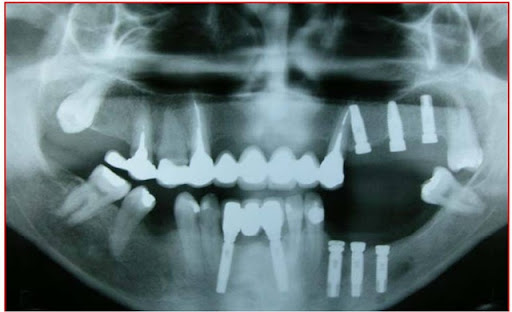

Radiograficamente, além do planejamento para os implantes, são avaliados todo o trajeto do nervo alveolar e a posição do forame mentoniano, utilizando-se da ortopantomografia, ou ainda de tomografia computadorizada (16).

Pode-se com isso fazer um traçado predicativo do local das osteotomias e, na tomografia, avaliar densidade do osso medular, a espessura das corticais e, as medidas precisas da posição do canal mandibular em todo seu trajeto

Fig. 1 - Radiografia ortopantomográfica mostrando o traçado do canal do nervo alveolar inferior.

Estudo radiográfico perfeito para a concretização da manobra cirúrgica, levando-se em consideração todos os detalhes da localização do plexo alveolar inferior e suas relações anatômicas (Figs. 2 e 3).

Figs. 2 e 3 – Aspecto radiográfico mostrando a perfeita localização do plexo alveolar inferior com as medidas corretas para a manobra cirúrgica com a localização do implante.

No pós-operatório são prescritas as orientações com o ferimento cirúrgico, antibioticoterapia, antiinflamatórios e analgésicos. São avaliadas periodicamente as alterações sensoriais e sua evolução, além dos controles radiográficos dos implantes (Fig. 14).

Fig. 14 - Controle radiográfico ortopantomográfico dos implantes e da alteração na anatomia mandibular.